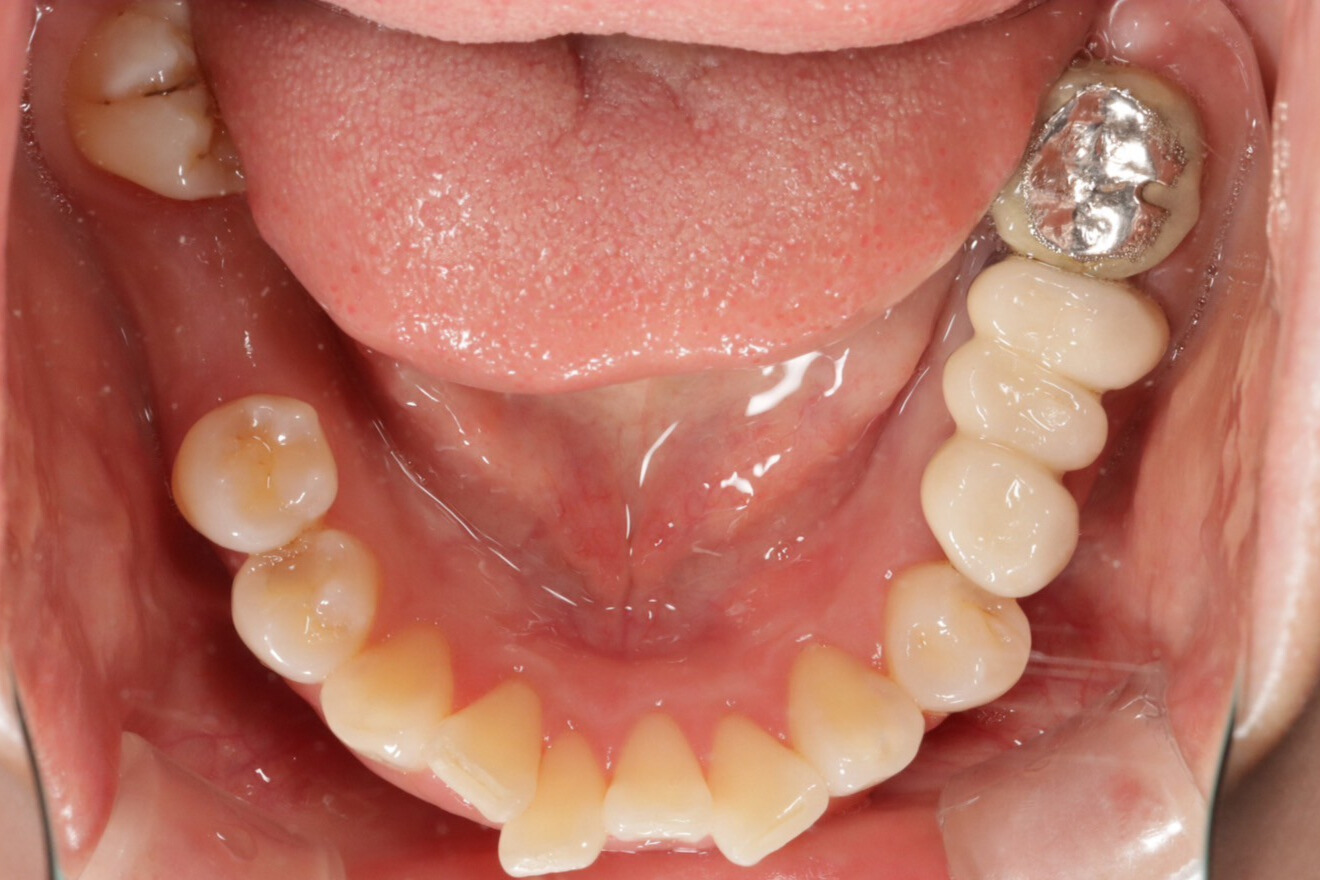

治療前